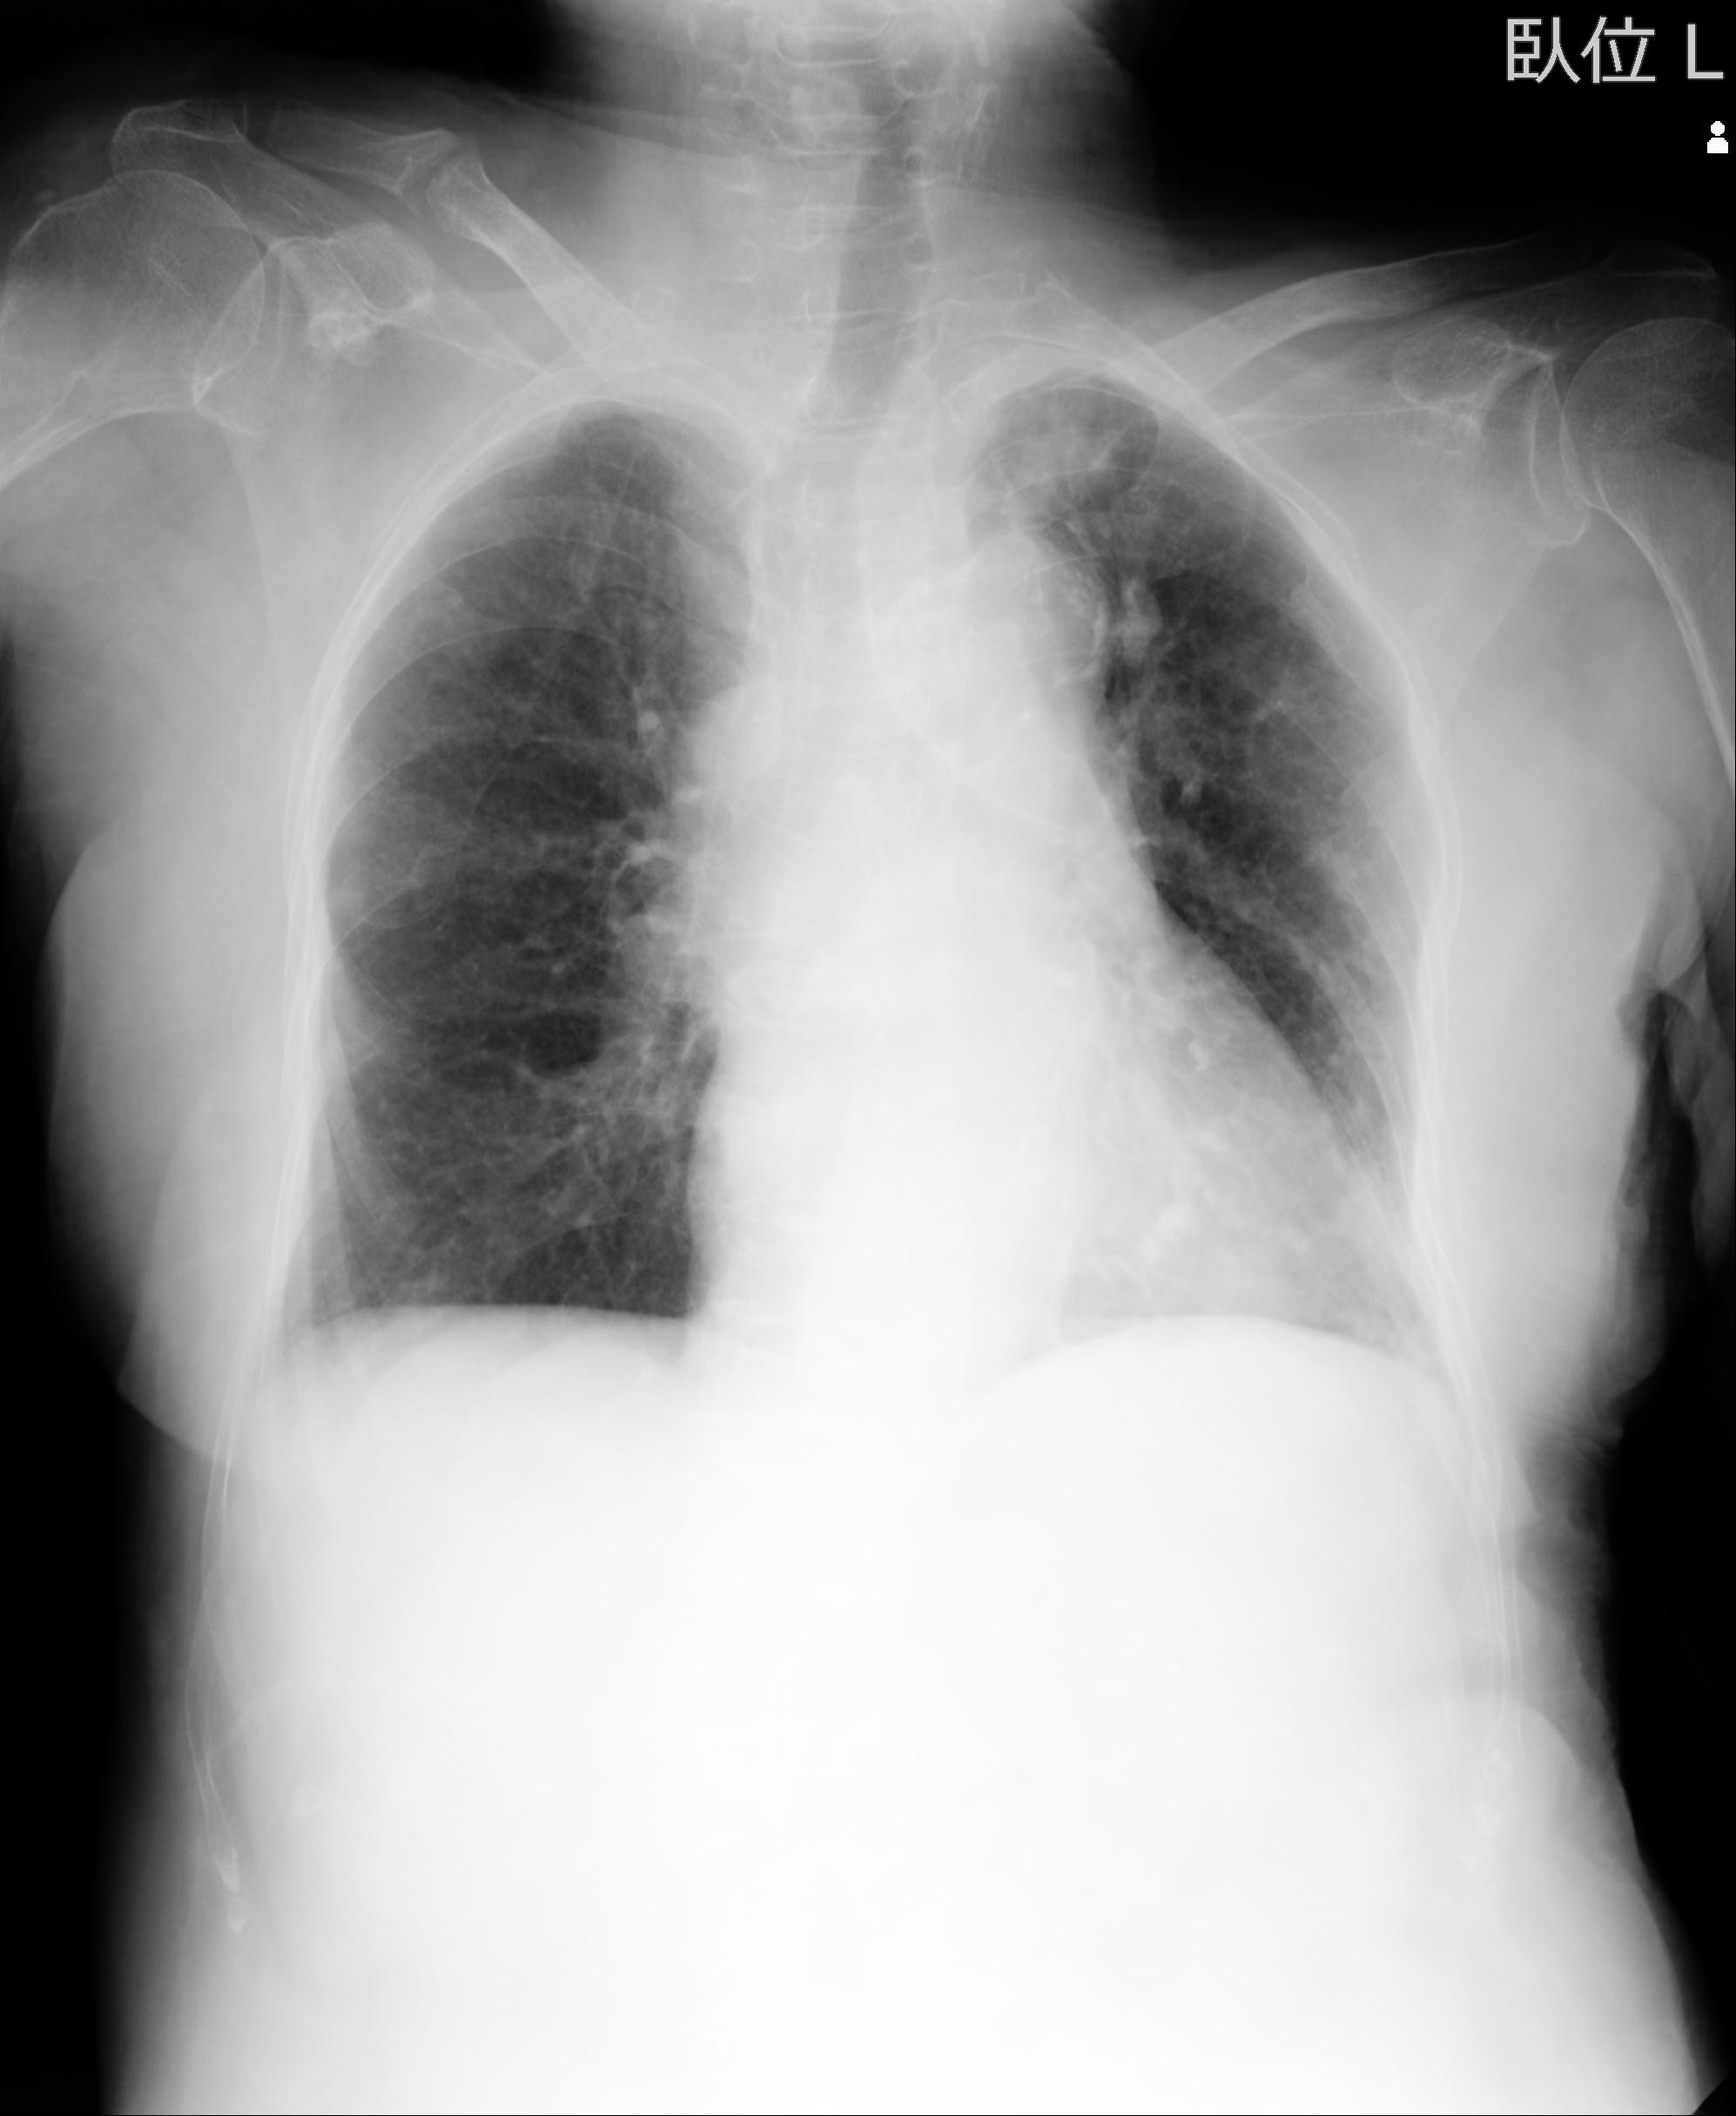

60058 3/9 11/4 右肩 2R+MRI 73歳男性 肩腱板損傷